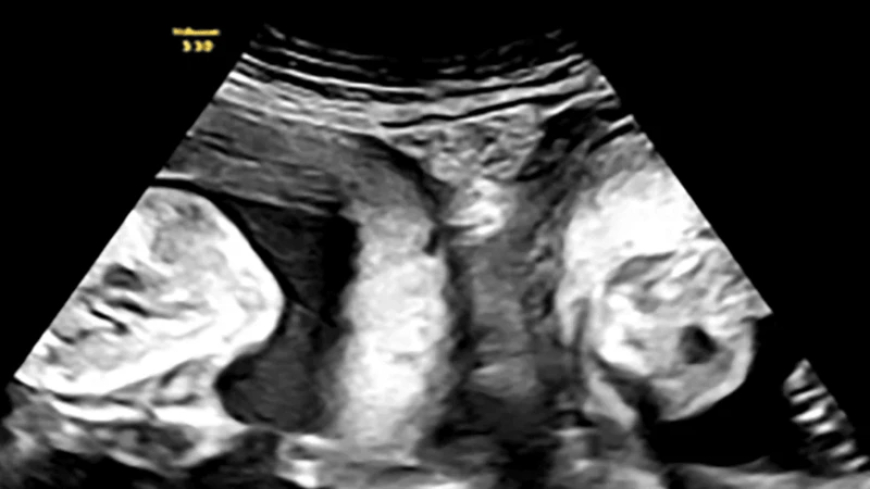

Uwo mubyeyi ufite uko yaremwe byihariye cyangwa se ufite umwahiriko udakunze kubaho kuko ngo kugira nyababyeyi ebyiri bishobora kuba ku mugore umwe mu bagore 2000, yabyaye izo mpanga mu kwezi gushize kwa Nzeri 2024, mu Bitaro byo mu Majyaruguru y’u Bushinwa, nk’uko byatangajwe n’inzego z’ubuzima ndetse n’ibitangazamakuru bya Leta byo mu Bushinwa.

Uwo mubyeyi witwa Li, yabyaye impanga z’umuhungu n’umukobwa, abyara abazwe mu Bitaro byitwa Xi’an biherereye mu Ntara ya Shaanxi, nk’uko byemejwe n’abayobozi b’inzego z’ubuzima aho mu Bushinwa, batangaje ko icyo gikorwa "ari igitangaza kimwe muri miliyoni".

Bubinyujije ku rubuga nkoranyambaga rwa Weibo rukoreshwa cyane aho mu Bushinwa, ubuyobozi bw’ibyo bitaro Li yabyariyemo, bwagize buti, "Ni ibintu bidasanzwe cyane kuba abana b’impanga barabayeho, buri mwana akaremerwa muri nyababyeyi ye, noneho igitangaje kurushaho ni uko bakomeje gukurira muri izo nyababyeyi zitandukanye kugeza bavutse”.

Ikinyamakuru BBC, cyatangaje ko ibyo Bitaro byabyaje Li, byemeza ko kuvukana nyababyeyi ebyiri ubwabyo ari ibintu bidakunze kubaho ndetse bifatwa nk’ibitangaza kuko ni ibintu bishobora kugirwa n’umugore 1 mu bagore 2000.